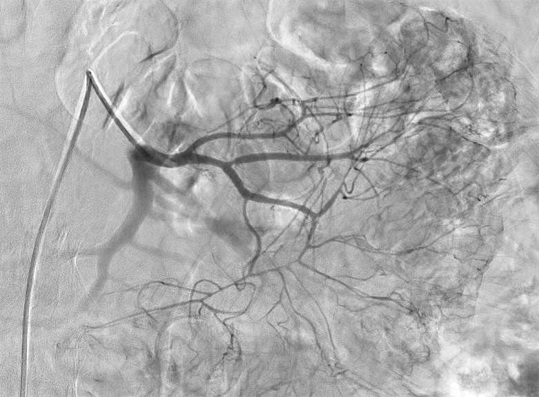

仍然不能确定具体出血血管 |

glue 0.1ml 注射后 |